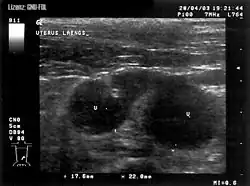

Eine Verdachtsdiagnose kann schon anhand der klinischen Symptomatik erfolgen. In der Vaginoskopie zeigt sich eitriges Sekret in der Scheide. In der Vaginalzytologie lassen sich neutrophile Granulozyten und Detritus nachweisen. Die endgültige Abklärung erfolgt mittels Ultraschall- oder Röntgenuntersuchung. Bei der Blutuntersuchung zeigen sich häufig eine Leukozytose mit Linksverschiebung und erhöhte Harnstoffwerte, aber auch eine Neutropenie kann auftreten. In einem Großteil der Fälle sind im abfließenden Sekret Bakterien, hier vor allem E. coli, Staphylococcus intermedius und Streptokokken nachweisbar. Ist eine medikamentelle Behandlung geplant, ist die Bestimmung der Progesteronkonzentration von Nutzen, denn der Einsatz mit Antigestagenen ist nur bei Progesteronkonzentration über 1,5 ng/ml sinnvoll.[4]